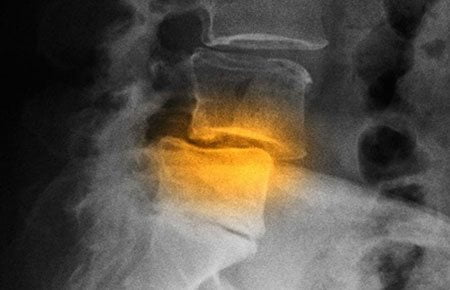

В народе распространено мнение, что мануальные терапевты вправляют «выпавшие диски». К сожалению, это массовое заблуждение. Межпозвонковые диски не могут выпадать. В них могут разве что формироваться грыжи, вправить которые невозможно.

Массаж и мануальная терапия эффективны при спондилолистезе – смещении позвонков. К сожалению, они оказывают лишь временное действие. В будущем съехавший позвонок скорее всего будет смещаться снова.